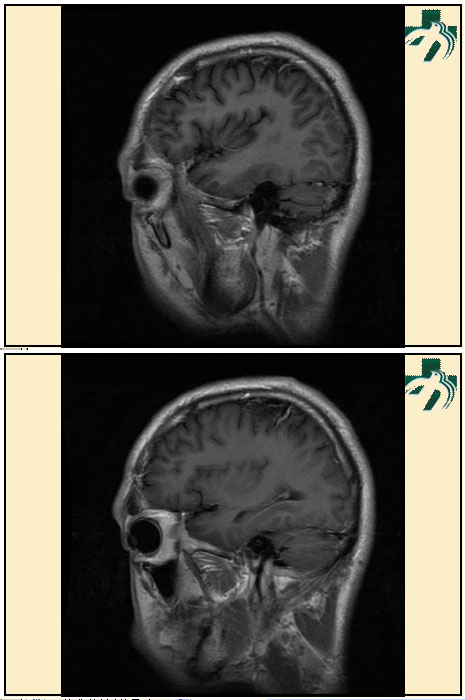

奴卡氏菌感染

第九期三博

读片会

病例之四

北京协和医院 提供

男性,22岁。自觉虫咬后皮疹、肢体麻木4月